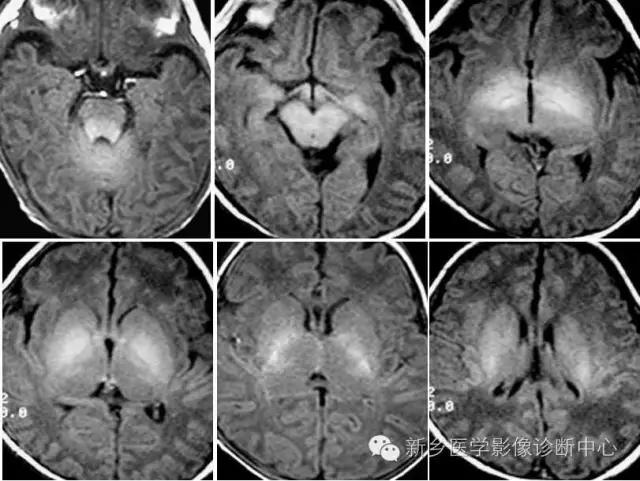

白质髓鞘形成后,与灰质在T1WI上成高信号相比较,T2WI成低信号。

在出生后6个月以内,T1WI是评估髓鞘化进展最有效的序列,与灰质相比,髓鞘化的区域在翻转恢复成像上成高信号;6个月以后绝大多数大脑白质在T1WI上成高信号,超过这段时间在评估髓鞘化过程就要依赖T2WI。到24个月时,除去位于枕顶叶侧脑室旁的终末区,髓鞘化的进程已大部分完成。这些终末区在长TR序列中呈模糊的高信号,这样的改变可以持续至30-40岁。

视放射、扣带回、禽距、小脑中部、小脑中脚、内囊前肢、胼胝体后部、膝部相继出现髓鞘形成。

生后5-6个月胼胝体高信号达到膝部。6个月时枕、顶叶出现高信号,并向额叶伸展。半卵圆中心髓鞘化更明显。

此时,白质内的水分逐渐下降,并有髓鞘形成,小脑半球、以至小脑叶、内囊全部、大脑枕叶、顶叶后部和额叶相继髓鞘形成和部分成熟。